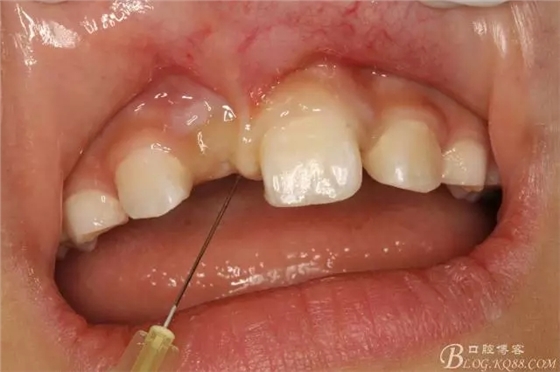

圖4.局部浸潤麻醉,左側(cè)21正常,11可在前庭溝處捫及隆起